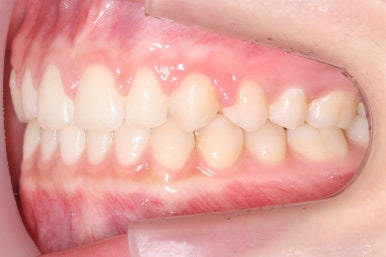

마무리 때의 사진입니다.

윗니만 부분교정하였지만 교합에도 이상 없이 매복되었던 송곳니는 매우 잘 위치를 잡았습니다.

부산매복치아교정 상악 부분교정을 통해 매복치를 교정해준 이번 치료의 전후사진 비교입니다.

썩은 유치 대신 영구치 송곳니는 매우 자연스럽게 위치되었습니다. 아랫니는 교정하지 않았기 때문에 약간 삐뚠 느낌은 남아있지만 맞물림은 크게 문제가 없게 마무리 되었습니다.